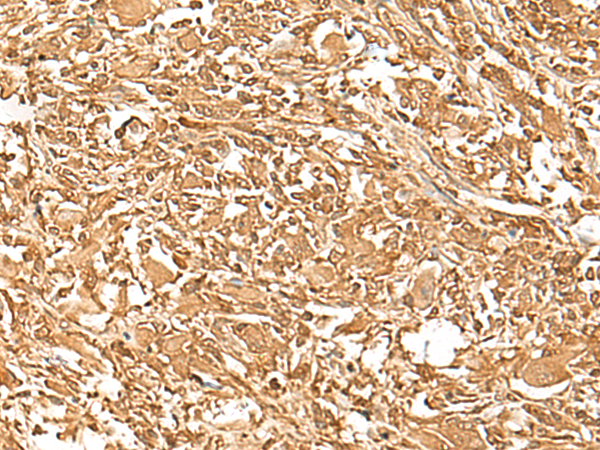

分类: 科研抗体货号: P13458别名: SCN2; GFI-1; GFI1A; ZNF163应用: IHC反应种属: Human, Mouse, Rat